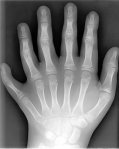

6º dedo